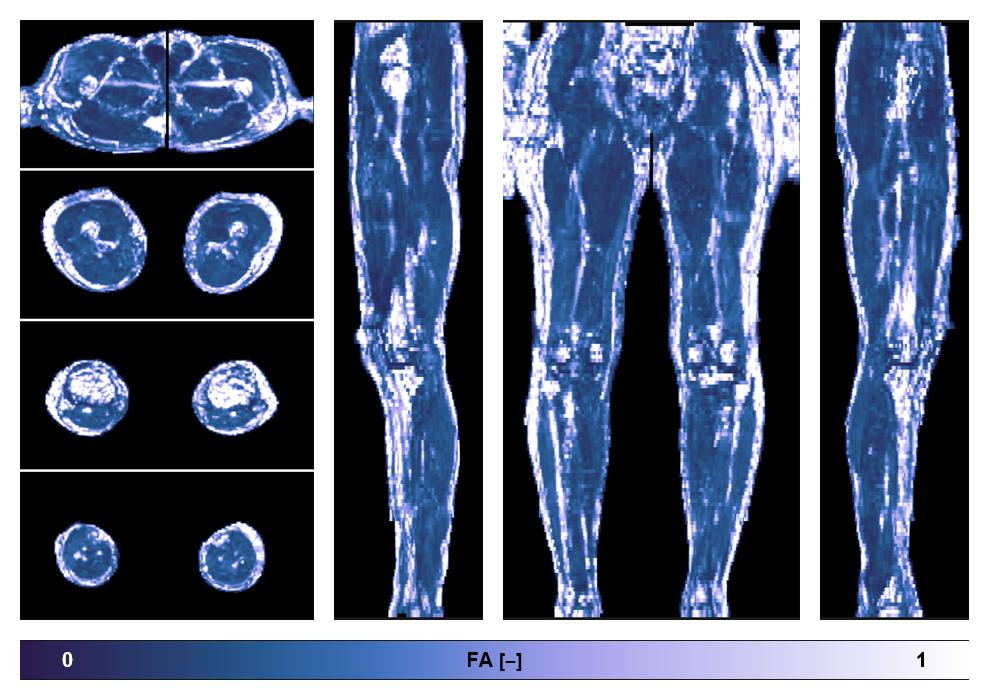

• Fractional anisotropy

IVIM corrected whole leg muscle fractional anisotropy obtained from diffusion tensor imaging.